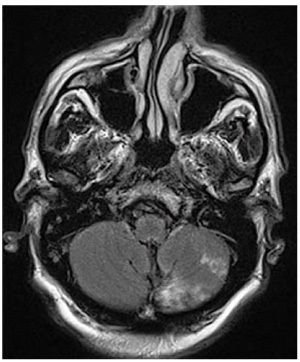

Quel est l’examen d’imagerie et la séquence? Quel diagnostic?

IRM séquence FLAIR infarctus cérebelleux gauche